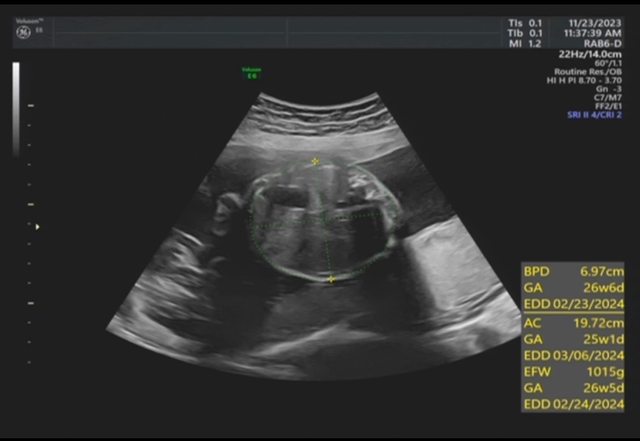

昨天去產檢,醫生覺得寶寶的胃偏大之後要注意觀察 我搜尋了一下好像只有看到胃太小的文,請問大家有沒有遇過類似情況? 我後來看了一下22週的高層次照片,那時候寶寶也是胃大大的,但那時只說是寶寶可能剛 吃飽 https://i.imgur.com/amlKp09.jpg

每一胎的狀況真的不一樣,這次第二胎先歷經羊水少週數小三週,到現在追到剩小一週, 但昨天醫生又提醒胃好像偏大,只希望二寶可以健康平安出生~ -- ※ 發信站: 批踢踢實業坊(web-ptt.tw), 來自: 101.12.24.40 (臺灣) ※ 文章網址: https://web-ptt.tw/BabyMother/M.1700797726.A.8D2